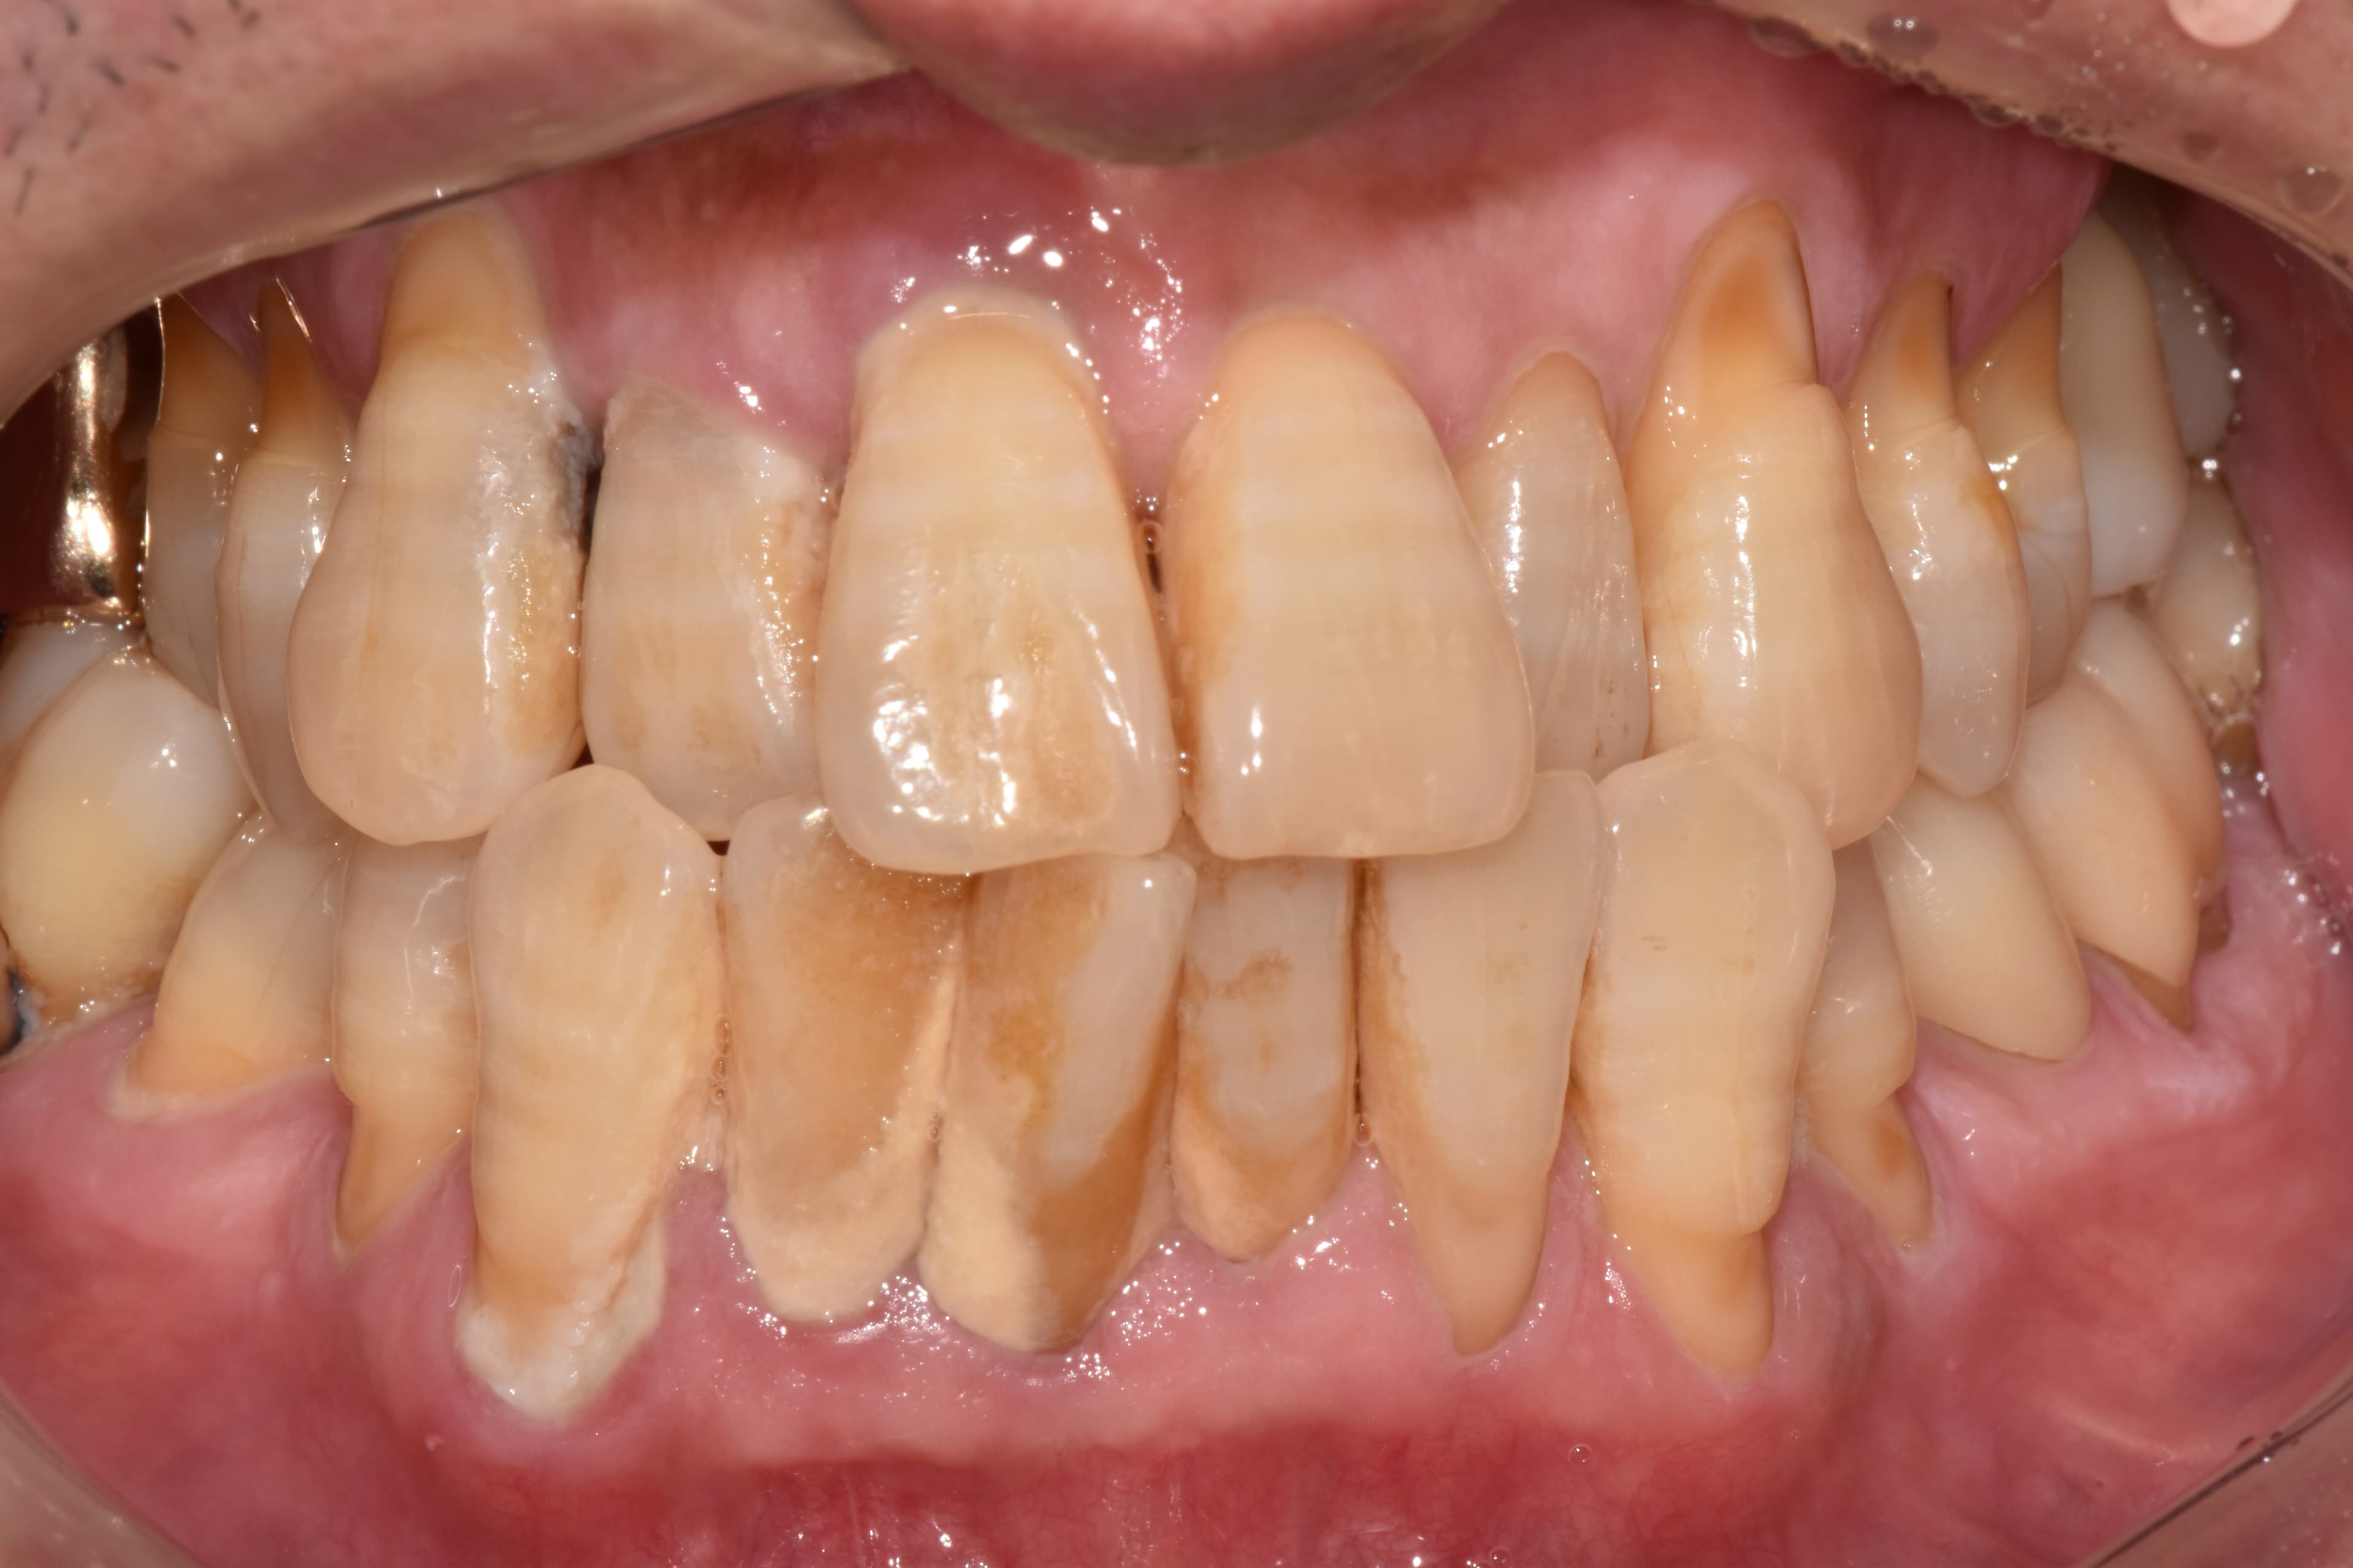

"多亏定期管理

50多岁所有牙齿都很健康"

Before

After

牙结石和牙龈炎症严重的状态

通过定期洗牙和管理保持健康